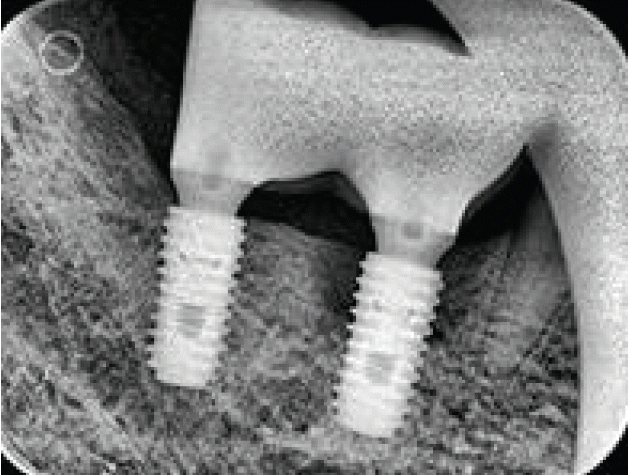

임플란트 식립 및 보철완성 후 유지관리시에는 다양한 부작용이 발생되며 이와 관련된 진료도 다양하게 적용되고 있다. 여기서는 치과건강보험과 관련된 고시 등을 기준으로 어떻게 적용할 수 있는지에 대하여 기술하고, 몇 가지 술식에 대하여 구체적인 방법을 소개하고자 한다.2005년까지는 국민건강보험요양급여의기준에 관한 규칙에서 치아의 보철치료(보철재료 및 기공료등 포함)는 비급여대상으로하고 있으며 보철의 범주에 속하는 임프란트 또한 비급여 대상으로, 임프란트시술 후 이와 직접 연관된 합병증 및 후유증 치료는 비급여토록 하였다. 2005년 5월 11일 진료평가심의위원회는 임프란트 치료시 최종철물을 장착하고 6개월이 경과한 후 발생한 임프란트 주위염, 임프란트 동요 및 파절 등은 이와 직접적인 진료로 보기 곤란하므로 요양급여로 인정키로 함으로서 한동안은 임프란트 주위염, 임프란트 동요 및 파절(Fig. 1) 등 3가지 경우에 한하여 기존의 건강보함항목을 적용받을 수 있는 근거가 마련되었다.따라서 이 시기에는 임플란트를술에 대하여, 간단하게 포셉으로 제거하는 경우에는 전치단순발치술 또는 구치단순발치술 등 식립된 임플란트의 위치에 따라 보험항목을 적용하였으며 버(bur)등으로 골삭제를 하면서 제거하는 경우에는 난발치 항목을 적용하고 버값(6,980원)을 청구하는 방식을 임상에서 사용하였다. 이후 2014년 7월 1일 임플란트 관련 항목(제거술, 치과건강보험적용기준)들이 신설되고(Table 1) [4], 후유증 인정기준에 대한 심사지침이 변경되었다(Table 2).